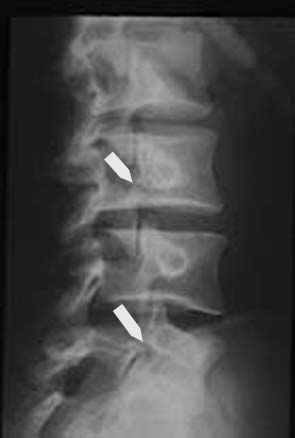

激しい運動や連続したジャンプなどを繰り返し行うことによる疲労によって腰などの脊椎に負荷がかかり文字通り分離してしまう症状の事です。

ちなみにそのまま放っておいてしまうと、分離した脊椎がずれてしまい【分離・すべり症】というもっと厄介な病気になってしまいますので気になる場合は整形外科などに行ってみるとよいでしょう

基本的には整形外科でレントゲン撮影して判別します